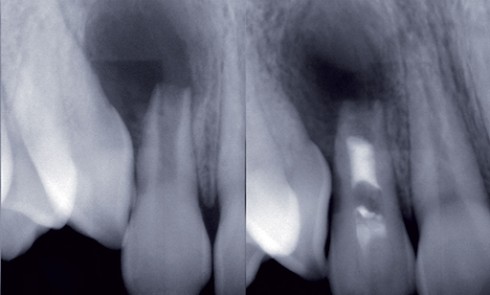

Odontologie restauratrice

Article réservé à nos abonnés Estimer l’état pulpaire

L’abandon des principes mécanistes de Black au profit d’une dentisterie a minima basée sur la préservation tissulaire couplée aux progrès...